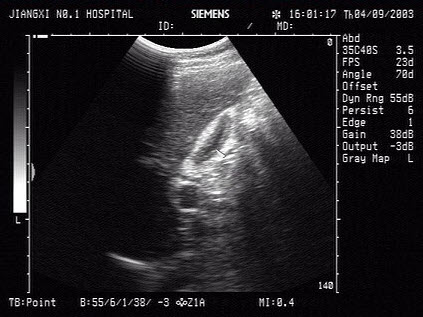

男性,37岁,睾丸红肿热痛,超声见睾丸回声不均匀,CDFI:血流信号丰富。如图所示,考虑为()

A.急性睾丸炎

B.附睾炎

C.睾丸脓肿

D.睾丸结核

E.睾丸肿瘤